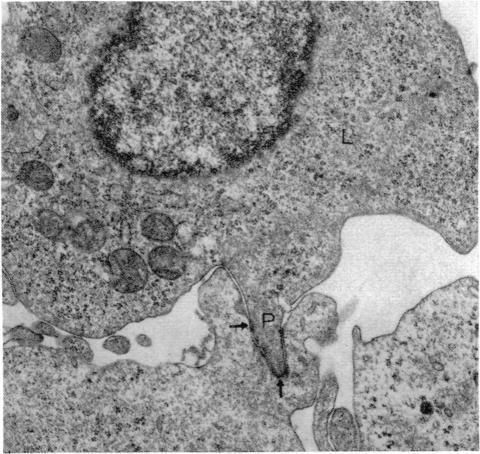

Interaction between pokeweed mitogen-stimulated secondary lymphocytes (PWM-lymphocytes) and target fibroblasts resulted in over 80 per cent adherence of the sensitized lymphocytes to the target cells. Adherence is by pseudopod penetration into target fibroblasts. The only lymphocyte cellular components found in the contact region were microfilaments. Cytochalasin B completely inhibited the specific adsorption of the PWM-secondary lymphocytes to the target cells. What adhesion did take place in the presence of cytochalasin B was found to be nonspecific. Ultrastructurally, the contact between lymphocyte and target cells was altered by the drug, when pseudopods were not observed. Possible effects of cytochalasin B on lymphocyte-mediated cytolysis, mainly by its effect on microfilament function, is discussed.

商陆丝裂原刺激的二级淋巴细胞(PWM淋巴细胞)与靶成纤维细胞之间的相互作用导致超过80%的致敏淋巴细胞黏附于靶细胞。黏附是通过伪足侵入靶成纤维细胞实现的。在接触区域发现的唯一淋巴细胞细胞成分是微丝。细胞松弛素B完全抑制了PWM二级淋巴细胞对靶细胞的特异性吸附。发现在细胞松弛素B存在的情况下发生的黏附是非特异性的。在超微结构上,当未观察到伪足时,药物改变了淋巴细胞与靶细胞之间的接触。本文讨论了细胞松弛素B对淋巴细胞介导的细胞溶解的可能影响,主要是通过其对微丝功能的影响。